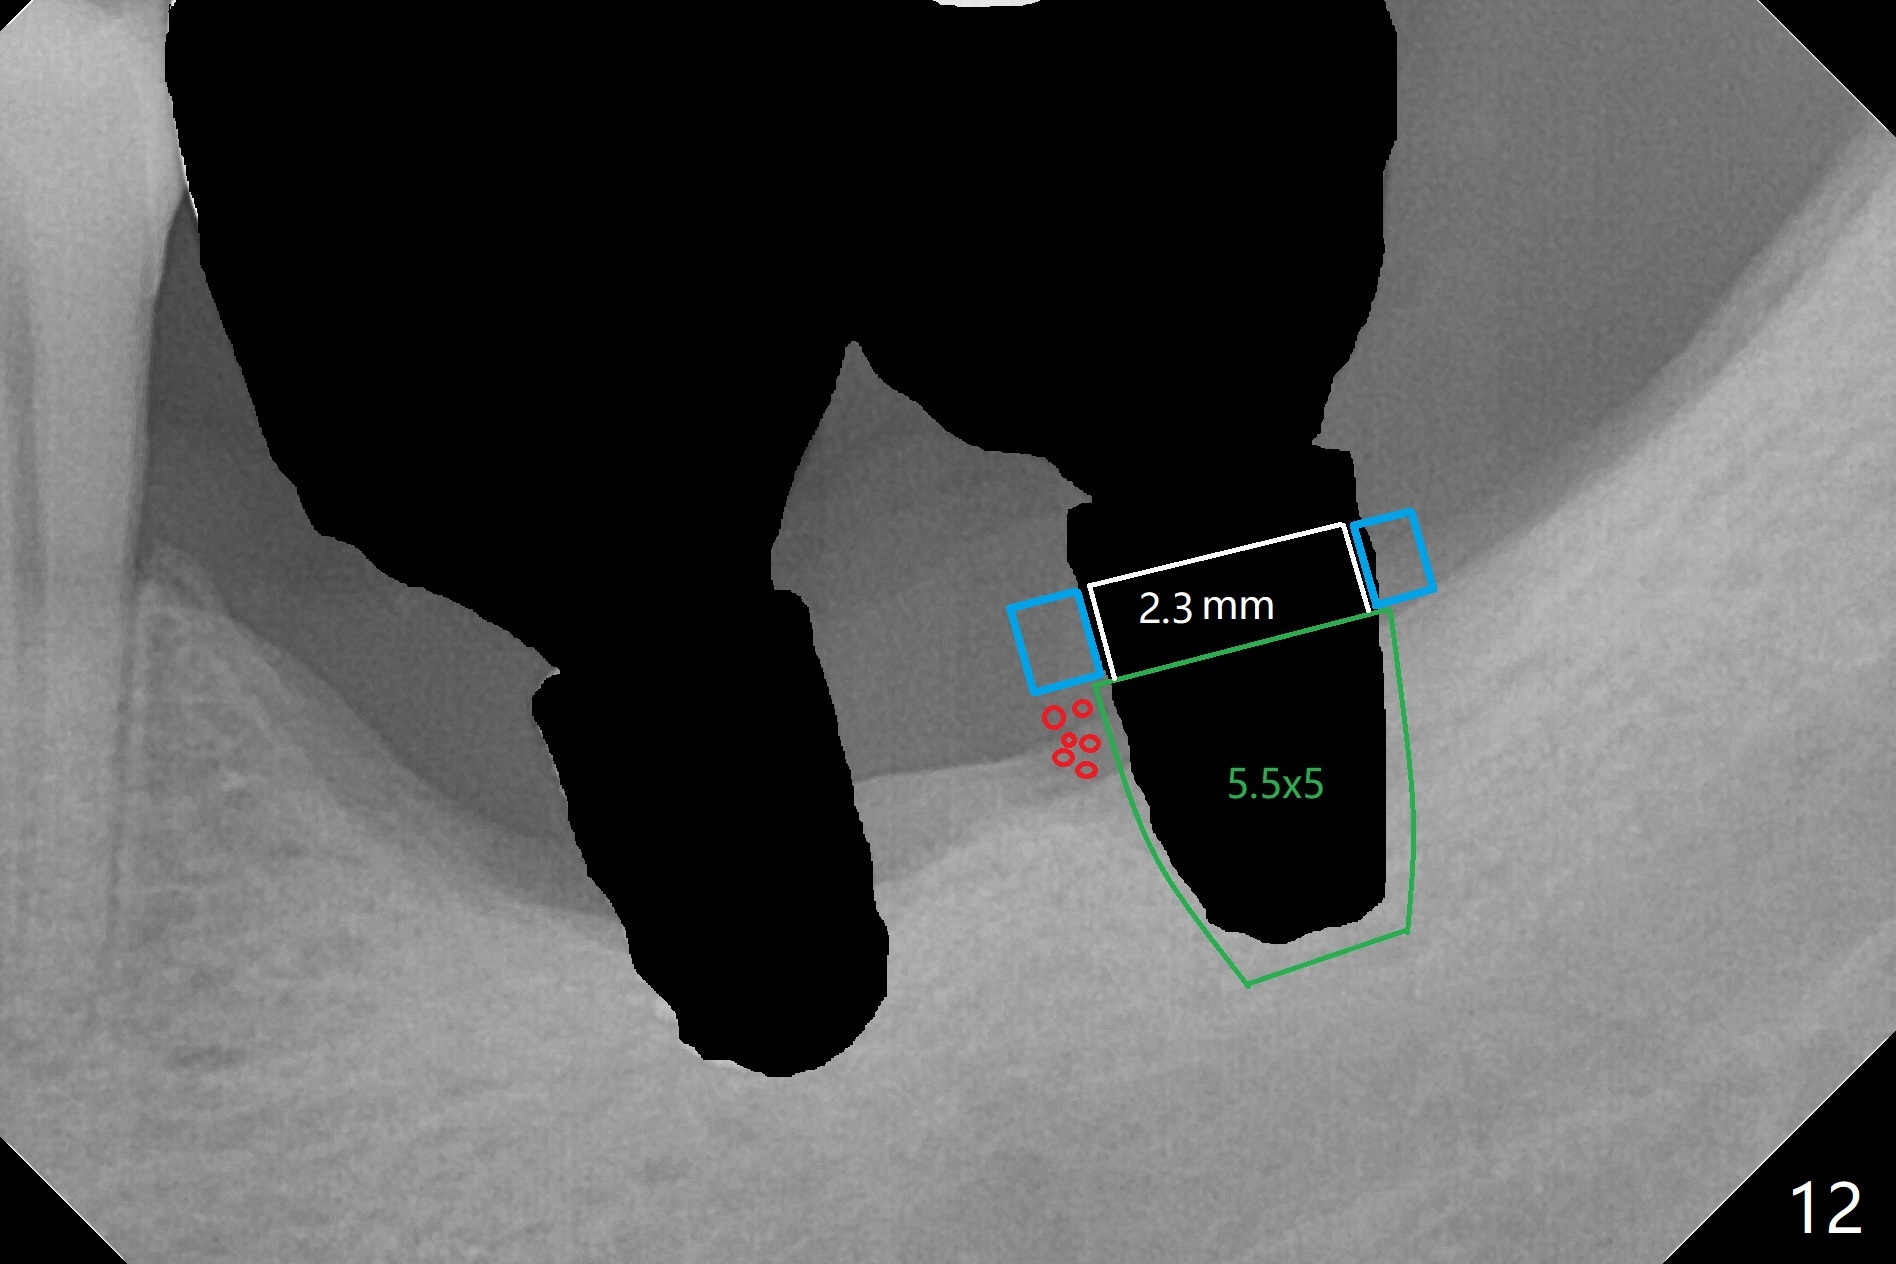

Preop photo shows severe mesial tilt of the tooth #18 (Fig.1). After extraction, the osteotomy is established in the apical end of the socket, where the buccolingual width is limited. It appears that an extra wide implant (5.9 mm) may perforate one of buccolingual plates. On the other hand, the buccal plate (Fig.2 double arrows) is intact and approximately 2 mm tall, whereas the lingual one is thin and lower. Initial osteotomy confirms that bone heights at #18 and 19 are 6 and 8 mm, respectively. Counting 2 mm of the buccal plate and bone graft lingually, a 8 mm long implant may be a practical option at the site of #18. After initial placement of two of 5x8 mm SM implants (Fig.3), the depth of the implant at #19 is adjusted twice (Fig.4,5). With placement of autogenous and allograft (Vanilla, Fig.5 *)) and abutments, a piece of cotton pellet is placed in each abutment well (access, Fig.6 *). Periodontal dressing is applied to the abutment wells for additional retention (Fig.7 *). Due to local poor oral hygiene, splinted provisional is fabricated 4 months postop (Fig.8) in preparation for limited orthodontic uprighting the tooth #20. The patient has pain with mastication at #18 eleven months post cementation (Fig.9). It appears that both of the implants should be removed with immediate replacement and bone graft. Prepare 4 PRF and sticky bone. The new implant will be 5.0 or 5.5x5 mm (Fig.10 green) with 2.3 mm platform (white). A block graft will be harvested from the ipsilateral ramus using 9/8 and 6/5 mm trephine burs for 2-3 mm in depth (Fig.11 blue). The ring graft will be seated around the platform over the implant (Fig.12).